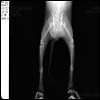

미추가 부러진 고양이 작성자 옥상... 작성시간 15.12.29 조회수 243